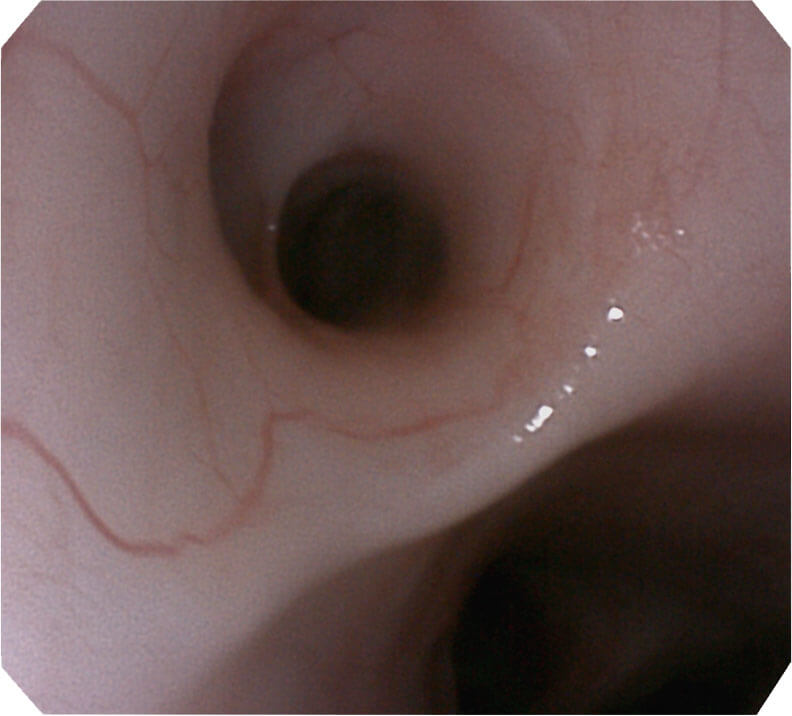

高分辨率画质

帮助医生更加清晰地观察气管表面病灶

光电复合染色成像技术

(Versatile Intelligent Staining Technology, VIST)

光电复合染色成像技术(VIST)是一种光学滤波和数字滤波相结合的染色成像技术,摒弃了滤光转轮而直接采用光谱组合的方案,加入了血红蛋白吸收高峰与次高峰的蓝紫光和绿光光谱,更有利于黏膜血管吸收,突显浅表层血管和中层血管的对比度,因而具备更高的图像对比度,有助于观察微细结构变化及病灶边界的观察。